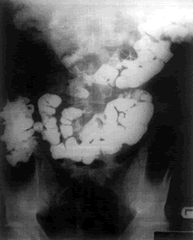

患者男性24岁,因脐周绞痛伴腹胀8年住院。患者经常出现脐周绞痛,持续数小时;但无与该病直接有关的其他病史。常规血液学检查、体检、乙状结肠镜检和钡灌肠均正常。钡餐检查显示,大部份小肠被包裹在上腹部1个卵圆形包块中,提示为肠疝(见图)。

打开腹腔后发现,只有小肠远端(约占全部小肠的1/3)位于腹腔,小肠其余部份被包裹在1个囊内,囊颈位于Treitz韧带上方的十二指肠空肠隐窝,部份位于胰腺前面。小肠和囊颈之间有粘连,分离横结肠系膜,将小肠轻轻拉出疝囊,缝合关闭疝囊。术后病人顺利恢复,8天后出院,至今一般情况良好。